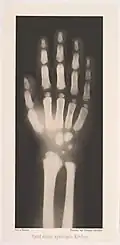

Main d'un enfant de 4 ans

Le chimiste contribue à la photographie par des articles co-écrits avec Josef Maria Eder sur les spectres des éléments chimiques. En 1894, il publie un livre sur la photographie interférentielle de Gabriel Lippmann et les améliorations qu'il y apporte. Il travaille dans le domaine des rayons X. Puis Valenta développe les premiers rayons X stéréo et publie un livre sur les papiers d'impression. Ses autres travaux comprennent l'utilisation du rouge de glycine et du violet d'éthyle comme colorants sensibilisants (1898-1899) ; l'analyse spectrale de centaines de colorants à l'aniline et de leur aptitude à filtrer la lumière et à imprimer des encres et des recherches sur la reproduction photomécanique[2].